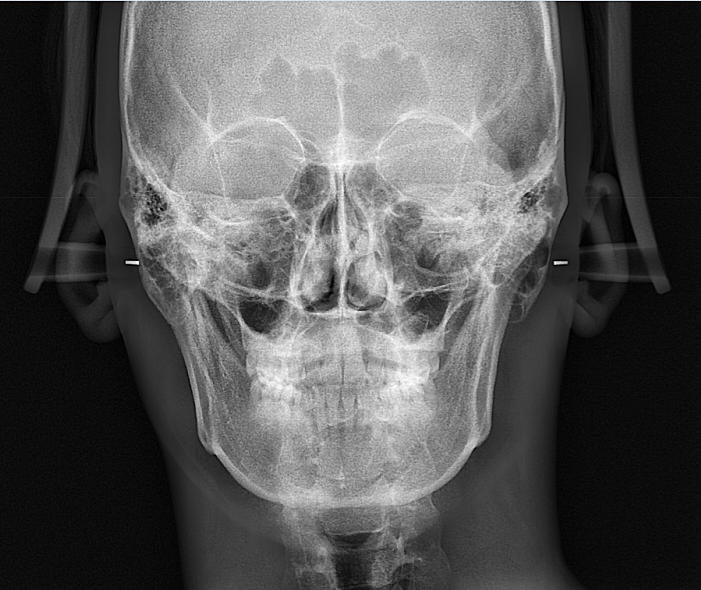

x-ray 중 파노라마에서 이 정도면 정상적인 범주에 속하며 비대칭이라고 할 수없습니다. 턱 좌우측 끝부위 각진부위도

좌우 비슷합니다. 정면상에서도 치아중심선도 맞으며 비대칭 소견 없습니다. 파노라마 사진을 돌면서 사진을 찍기 때문에

찍을 때 마다 좌우가 조금씩 다르게 나타납니다.

사람은 완전히 좌우 대칭이지 않습니다. 연조직이나 골격에 의해서 좌우가 조금씩 달라 보일 수 있습니다. 골격적으로 condyle 부분이 비대칭이지 않다면 canting (기울임)도 나타나지 않습니다.

특히 2~3mm 정도의 틀어짐은 정상인들이라면 그 차이를 쉽게 느끼지 못합니다. 현재 사진으로서는 정상 범주에 속하게 되며 특별히 문제가 되는 정도는 아닙니다.